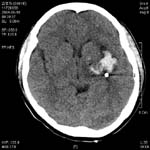

<ÇãÇ÷¼º

³úÁ¹Áß>

ÁÂÃø

Áß³úµ¿¸ÆÀÇ Æó»öÀ¸·Î ÀÎÇÑ ³ú°æ»ö¼Ò°ß(Ç÷°üÁ¶¿µ¼ú»ó

Áß³úµ¿¸ÆÀÌ º¸ÀÌÁö ¾Ê°í ÀÖ´Ù)